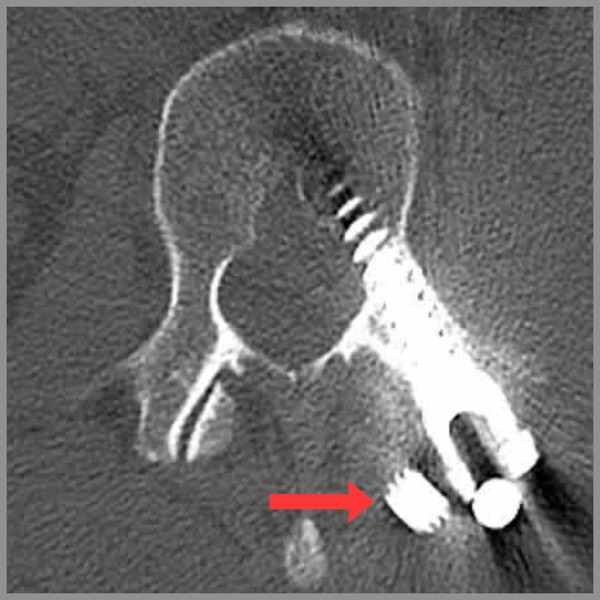

- Severe burst fracture of T12, plus some crush and/or burst damage to L1, L2, so they bridged all of those vertebrae with impressive chunks of metal on either side of spine, screwed into vertebrae, and a long steel bar screwed into her upper arm with several screws ... “carpentry” surgery! Girl’s got gear!

Amy’s back contained a bunch of surgically implanted titanium — bracing on the inside, two vertical bars that spanned the broken joint like rails attached to fence posts driven into the bones above and below. We always just called her implants the bars, as in “How are the bars feeling today?”

One of the bars had come out of its post socket. This was plainly visible on an MRI scan of her back — but missing from the radiologist’s report. I found it myself, staring at those magical black and white transverse slices of my wife’s back, which clearly revealed cross-sections of a screw (so unlike any anatomy!) floating in the wrong place, the end of the of one bar well out of place… and the other one on the verge of coming loose as well. I am proud of making that discovery, even though it is not really as amazing as it sounds. Certainly it’s a minor embarrassment for the radiologist, but mostly his attention was properly on my wife’s bones and spinal canal, not so much her implants.

The find was soon confirmed by a surgeon, who was more amused than shocked. “It’s rare. Less than 5% probably,” he explained. “But it does happen, and it’s really not that big a deal.” The bars are simply an internal brace, and are more or less useless dead weight once the bone has healed (if not long before that).